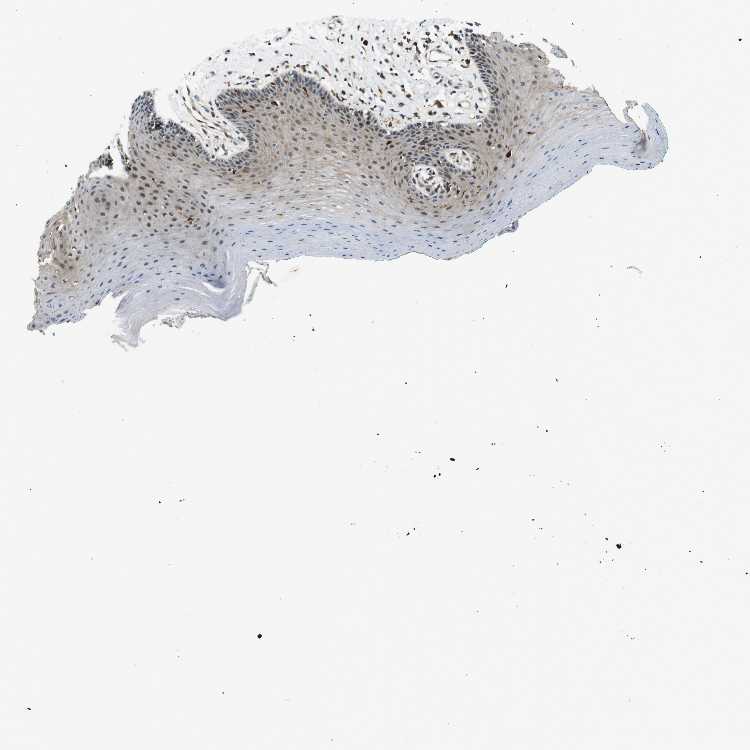

TISSUE PRIMARY DATA ORAL MUCOSA Show tissue menu

ORAL MUCOSA - Antibody stainingi

Antibody staining in the annotated cell types in the current human tissue is reported as not detected, low, medium, or high, based on conventional immunohistochemistry profiling in selected tissues. This score is based on the combination of the staining intensity and fraction of stained cells.

Each image is clickable and will lead to virtual microscopy that enables deeper exploration of all samples and also displays staining intensity scores, fraction scores and subcellular localization as well as patient and tissue information for each sample.

Antibody HPA015696Antibody HPA017343

Squamous epithelial cells MediumMedium